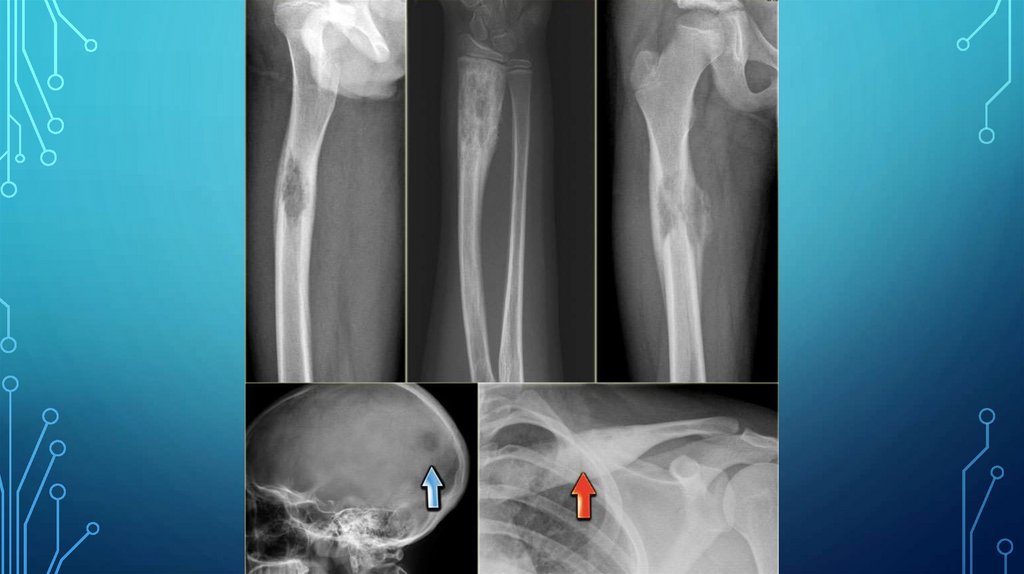

R-КАРТИНА:

• Определяется деструкция кости. Очаги деструкции одиночные и

множественные, часто сливного характера. Может быть поражена одна кость

или несколько костей одновременно. Форма очагов деструкции

разнообразная — округлая, неправильно овальная, но чаще картообразная.

Диаметр очагов деструкции от 0,5 до 5 и более см. В случаях сливного

характера очагов деструкции могут прослеживаться костные перемычки.

Контуры очагов деструкции, как правило, четкие. Очаги деструкции в

отдельных случаях могут быть окаймлены ободком склероза. Очаги

деструкции исходят из костного мозга, но быстро изнутри прорастают и

компактную ткань. Кортикальный слой неравномерно истончается.

• При локализации очага деструкции в диафизе длинных трубчатых костей

возможна периостальная реакция.